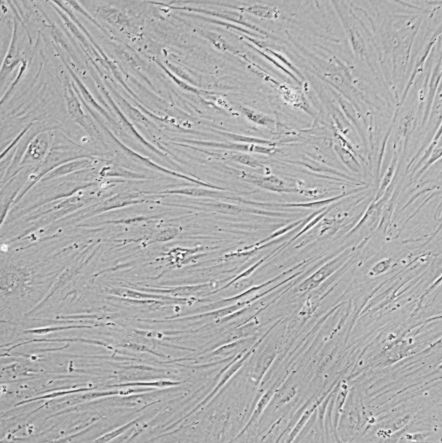

细胞名称:CCD-1097Sk_III级浸润性导管癌患者的乳腺正常皮肤细胞

细胞形态:成纤维细胞样

培养条件:EMEM + 10% fetal bovine serum (FBS)+1%P/S

37 ℃, 5% CO2

传代方法:1:3~1:4传代, 3-4天传1代